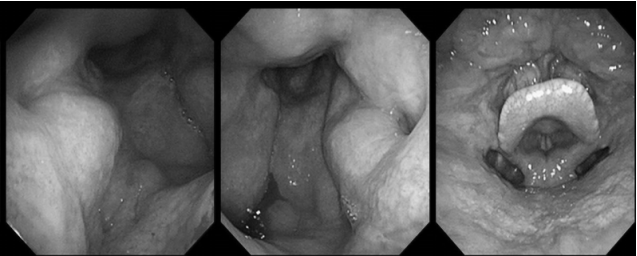

耳内镜检查:分泌性中耳炎(右)

电子喉镜检查:鼻息肉(双)

双耳鼓膜完整,右侧鼓膜内陷明显,右侧鼓室可见积液